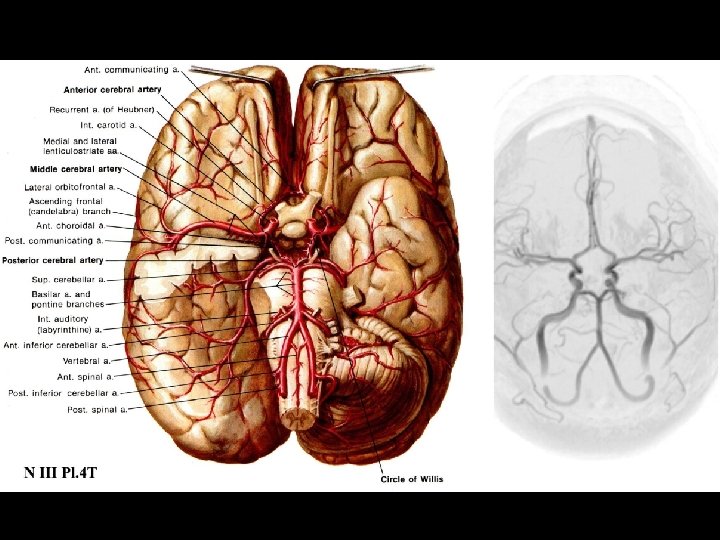

Arterial Blood Supply Arterial Blood Supply

Anterior circulation Internal carotid arteries Posterior circulation Vertebral arteries Anterior circulation Internal carotid arteries Posterior circulation Vertebral arteries

Anatomy and Vascular Territories of the 3 Main Cerebral Arteries: Middle Cerebral Artery Anatomy and Vascular Territories of the 3 Main Cerebral Arteries: Middle Cerebral Artery

Anterior Cerebral Artery and Posterior Cerebral Artery Anterior Cerebral Artery and Posterior Cerebral Artery

Cortical Areas Supplied by the MCA, ACA and PCA Cortical Areas Supplied by the MCA, ACA and PCA

Superficial and Deep Arterial Supply to the Cerebral Hemispheres Coronal Plane Superficial and Deep Arterial Supply to the Cerebral Hemispheres Coronal Plane

Superficial and Deep Arterial Supply to the Cerebral Hemisphere Axial Plane Superficial and Deep Arterial Supply to the Cerebral Hemisphere Axial Plane

Lenticulostriate Arteries Supply the Basal Ganglia and Internal Capsule Lenticulostriate Arteries Supply the Basal Ganglia and Internal Capsule

Arterial Supply of the Thalamus and Basal Ganglia Arterial Supply of the Thalamus and Basal Ganglia